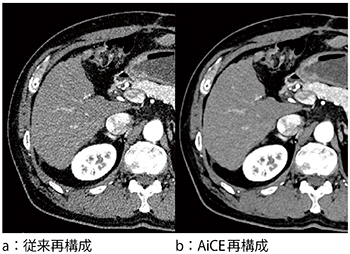

当社は,世界に先駆けてAIを用いて設計した画像再構成技術“AiCE(Advanced Intelligent Clear-IQ Engine:エース)”を高精細CT「Aquilion Precision」に搭載した。AiCEは,ディープラーニングを用いて設計されたノイズ成分とシグナル成分を識別する処理で,分解能を維持したままノイズを選択的に除去する再構成技術である。AiCEには,DCNN*1のディープニューラルネットワークを用いており,DCNNにどのような学習をさせるかが精度に大きく影響を与える。AiCEの特筆すべき点は,DCNNの学習にMBIR*2である“FIRST*3”再構成による高品質なデータを教師画像とすることで,大幅なノイズ低減と空間分解能の向上を実現している(図1)。また,FIRSTに比べ大幅に計算量を削減することができ,再構成時間の高速化を実現している。

図1 従来再構成とAiCE再構成の画像比較

(データご提供:国立がん研究センター中央病院様)